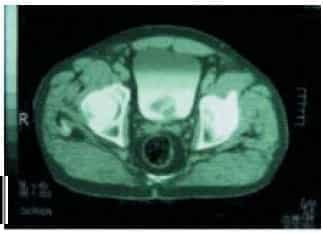

TAC abddominopélvico: Imagen intravesical hiperdensa con estructura metálica.

Se realiza cistolitotomía abierta sin complicaciones.

Lito de 6cm por 4cm. El análisis del cálculo comprobó la presencia de dispositivo intrauterino.